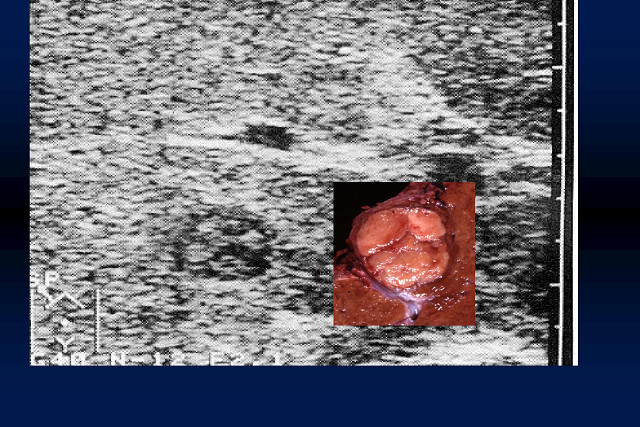

大きな関心事だと思います。「がん」はその最たるものですが、エコーではカラードプラ法が

威力を発揮するということを、画像を示して説明していただきました。

血流の向きと速さをカラー画像で表示することにより、多血性か乏血性かで、腫瘍の種類を

区別することができるというお話でした。